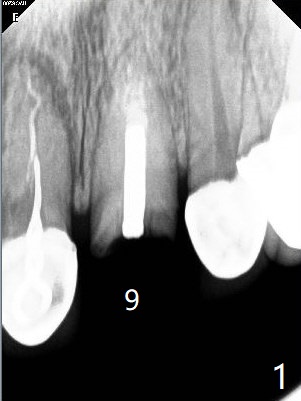

A 51-year-old woman with poor dentition has history repeated dislodged crown and post at #9. Finally the post fracture (Fig.1). After discussion of treatment options, she chooses to save the tooth. Treatment plan is to remove post, possible RCT retreatment, redo post and crown. The post remains stable following lengthy use of Piezo scaler (Fig.2). It appears that Piezo is quite aggressive, removing the tooth structure and the metal. Finally the coronal portion of the post is removed for cast post (Fig.3). There is approximately 2 mm for ferrule effect (Fig.4). The cast post is cemented with RelyX Ultimate and prepared for crown (Fig.5-7).